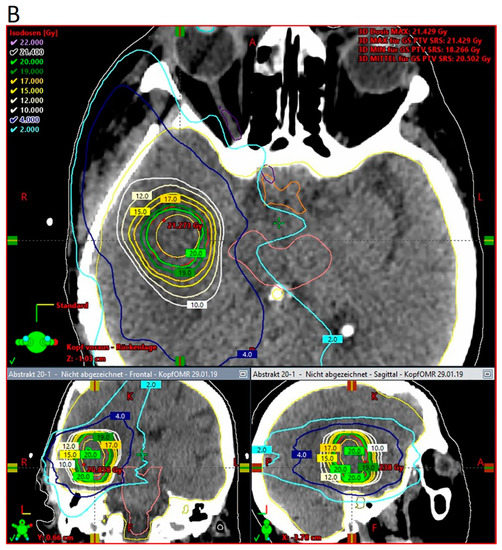

According to pathology-based reports on tissue infiltration surrounding BM, a clinical target between 1 and 4 mm should be considered in the radiotherapy adjuvant setting, depending on the primary histology [33,35]. With approximately 80% of the prescribed surface dose at 3 mm from the surface, kV IORT provides an outstanding treatment outline while avoiding the usually large volumes required during adjuvant SRS. Subsequent dosimetric comparisons between IORT and SRS as dose-escalation strategies for resected glioblastoma and BM, respectively, demonstrated up to three times lower brain V12G (volume of brain receiving 12 Gy) results, favoring IORT [181,182]. An exemplary dosimetric comparison between both modalities is displayed in Figure 2 [181].

Figure 2.

Three-dimensional view of dose distribution profiles, comparing (A) IORT and (B) SRS for the same target. Reprinted with permission from Sarria et al. [181]. Copyright year 2021, copyright owner’s name Sarria et al. Under the terms of the Creative Commons Attribution License (CC BY) [181].